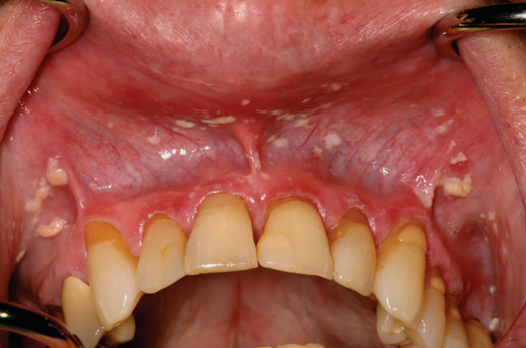

Liquen Plano Reticular